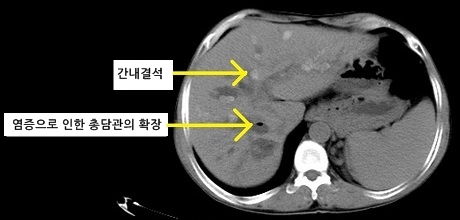

대표적으로 시행하는 영상의학 검사는 복부 전산화단층촬영(CT)이나 복부 자기공명영상(MRI)입니다. 쓸개를 확인하는 데 도움이 되는 복부 초음파는 상대적으로 담관을 확인하기 어렵다는 단점이 있기 때문에 우선 시행하지는 않습니다.

담관염 CT 소견 (출처 : 위키미디어)

담관염을 확인할 수 있는 가장 중요한 검사는 역행성 췌담관 내시경 검사(ERCP)입니다. 내시경을 통해 십이지장까지 접근해서 담관을 확인할 수 있습니다. 담즙이 고여서 담관이 확장된 것을 확인할 수 있고 더불어 정확한 진단과 동시에 치료까지도 한 번에 할 수 있다는 장점이 있습니다. 요즘에 가장 선호하는 검사법입니다.